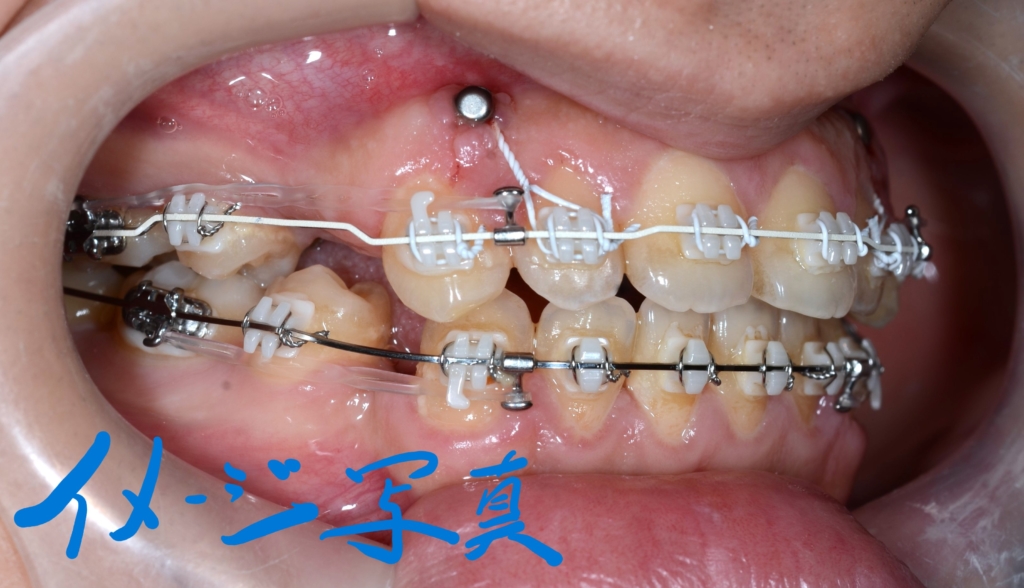

同じ内容の治療をしている方のモノをイメージ写真として挙げています。

上下とも抜歯により得られたスペース分を引っ込めたのですが、噛み合わせの辻褄合わせよりも、口元を少しでも大きく引っ込める!ことを優先しました。

結果として、出っ歯がちょっと残ってしまいました。

そこで、上の歯列全体をより後方へ移動させることで、より引っ込んでいる下の歯列に合わせることで、口元も引っ込めることにしました。

先ずは、その準備として上顎の口蓋にアンカースクリューを追加で植立します。

口蓋のアンカースクリューにPLAS&パラタルバーをセットして、上の歯列全体を後方へ移動させます。